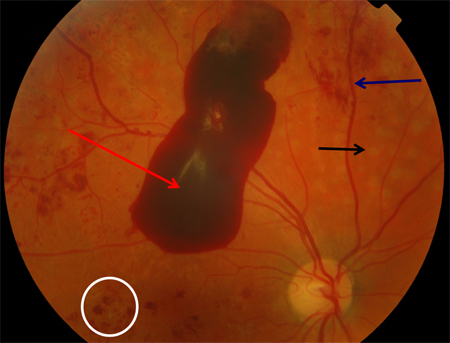

Proliferative diabetic retinopathy: retrohyaloid haemorrhage (red arrow), venous beading (blue arrow), cluster haemorrhage (white circle), pan-retinal laser burns (black arrow)

Courtesy of Moorfields Photographic Archive; used with permission